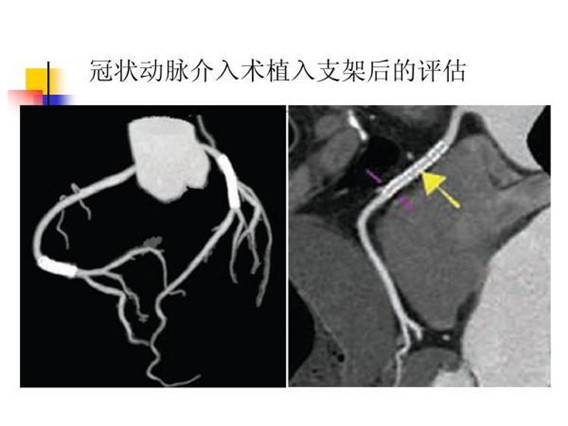

CTA成像检查在临床上可用于:(1)心脏表面成像:观察心脏表面形态、瓣膜结构、心肌厚度、心脏长短轴分析;(2)冠状动脉树成像:能显示冠状动脉的3-4级分支,可诊断冠状动脉狭窄、动脉粥样硬化、评估冠脉内支架和搭桥术后疗效;(3)分析和评估心脏功能,如心机灌注情况、左心室射血分数、室壁运动等(4)冠状动脉钙化积分:可对冠状动脉钙化进行精确定量,评估冠状动脉钙化程度和范围,是对冠心病进行早期普查的理想的无创的检查方法。CTA与传统动脉插管血管造影(DSA)相比,具有安全性高,检查过程便捷,费用低廉等优势。